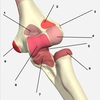

2

3

4